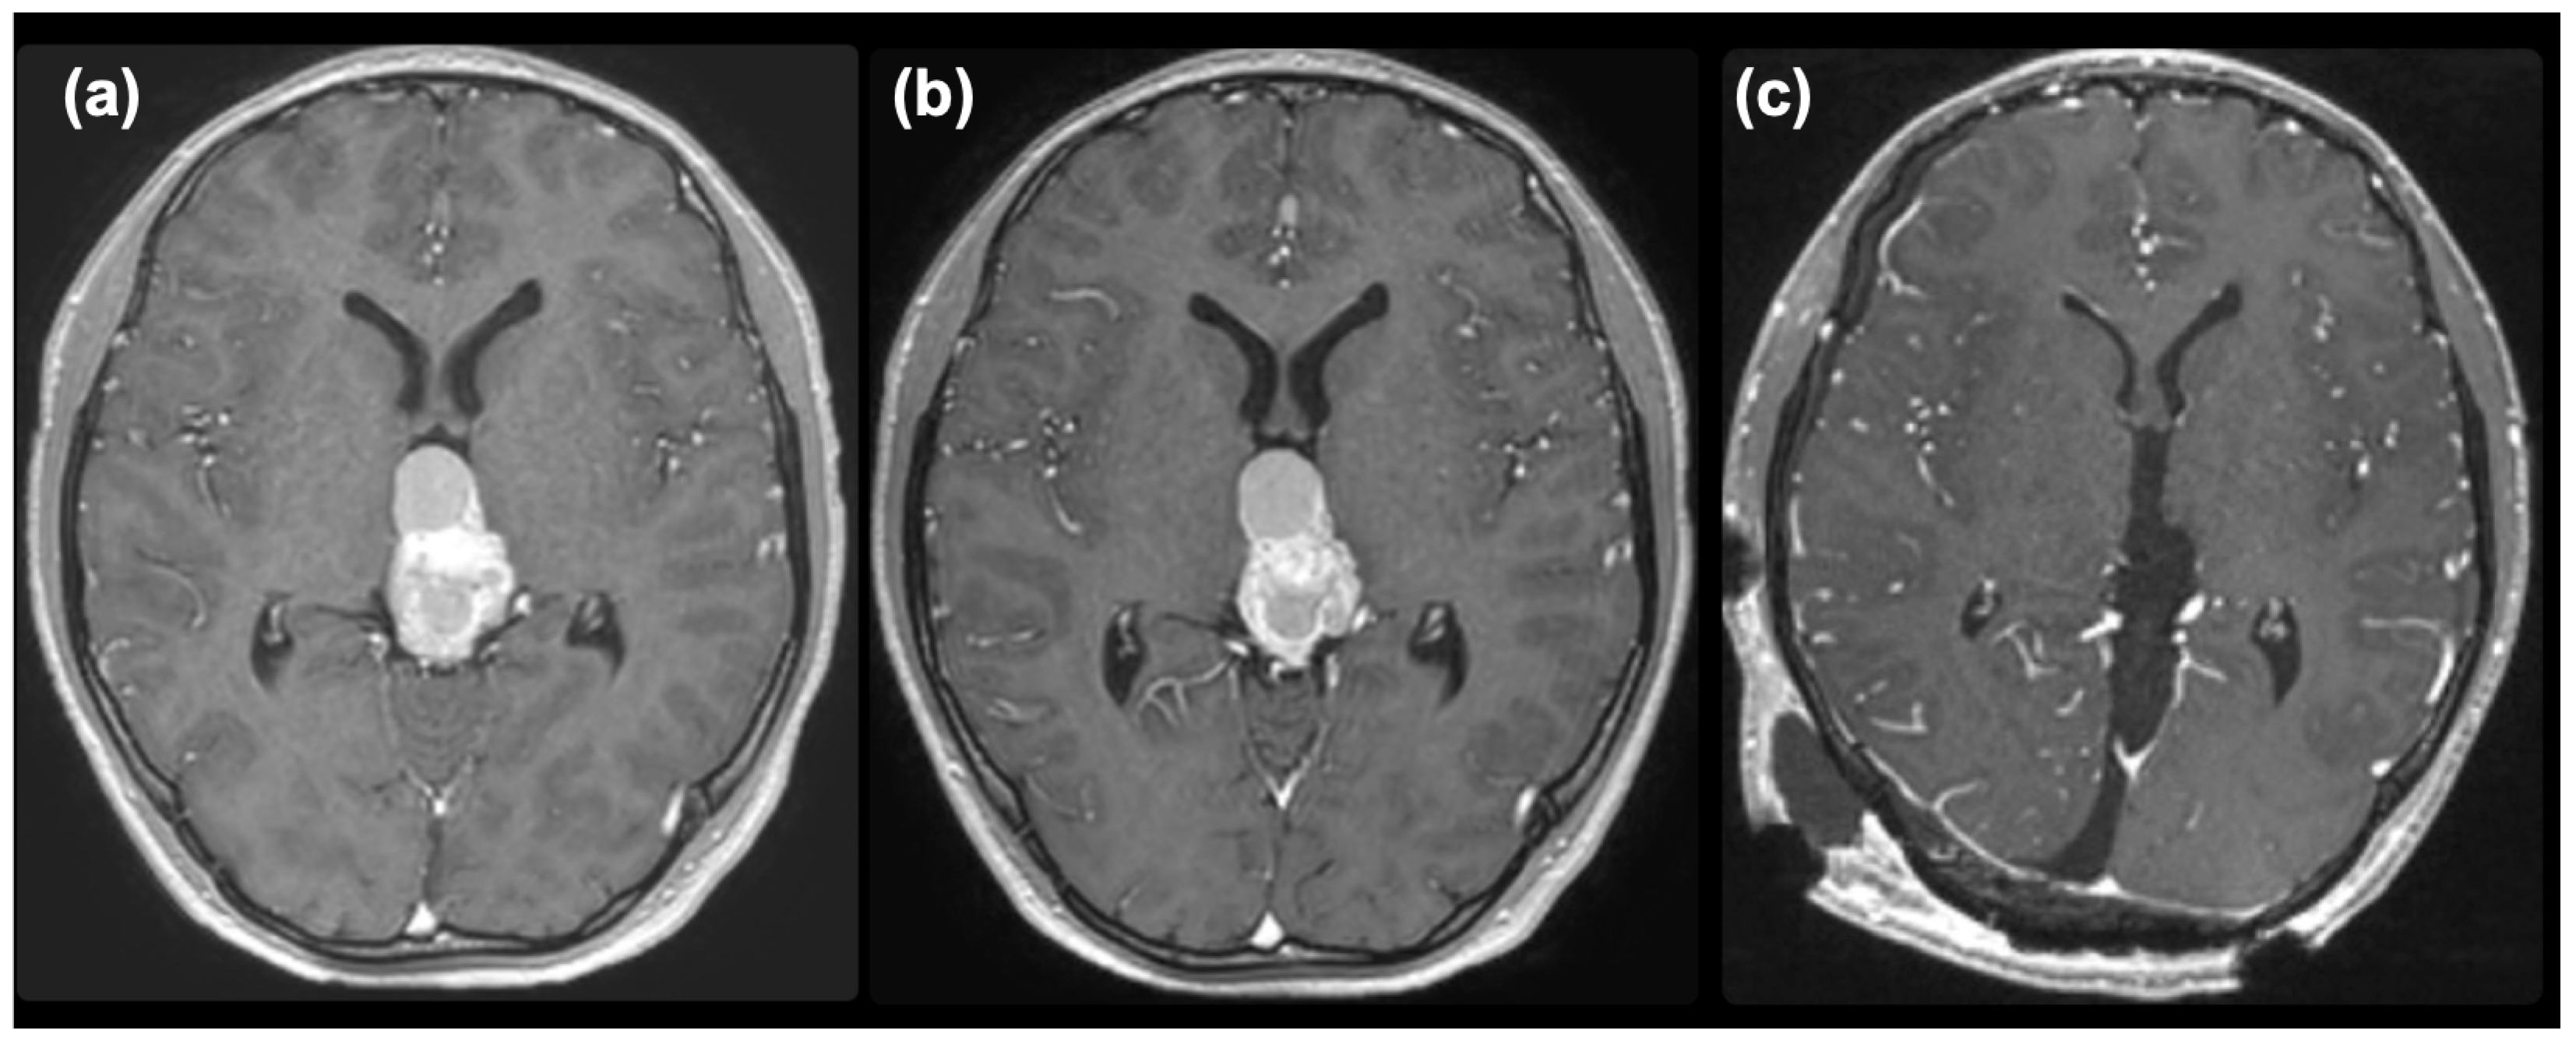

2. Case Presentation